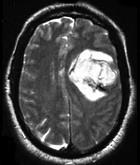

- 单项选择题男,52岁, 既往检查有脑动静脉畸形,突发站立不稳伴恶心呕吐4小时, 请结合影像图像选择最可能的诊断 ( )

A、脑出血

B、脑脓肿

C、脑转移瘤

D、脑梗死

E、颅内动脉瘤